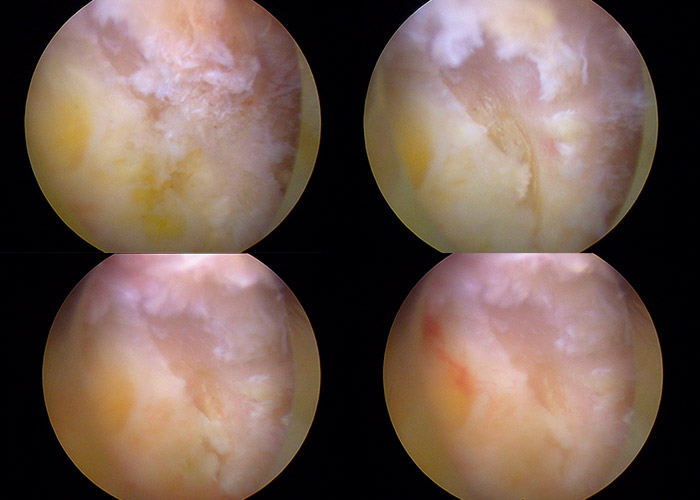

Posteriormente se procede a la identificación de la compresión en el canal medular. Se comienza la retirada del ligamento amarillo de la región central para descomprimir las estructuras neurológicas.

Se procede al acceso al lado contra lateral, mediante el mismo portal posterior derecho, para liberar las estructuras neurológicas del lado izquierdo y comprobar la adecuada liberación y descompresión.

Se procede a la cobertura de la cura expuesta mediante Lioplan.

Por último, se le infiltran corticoides locales.